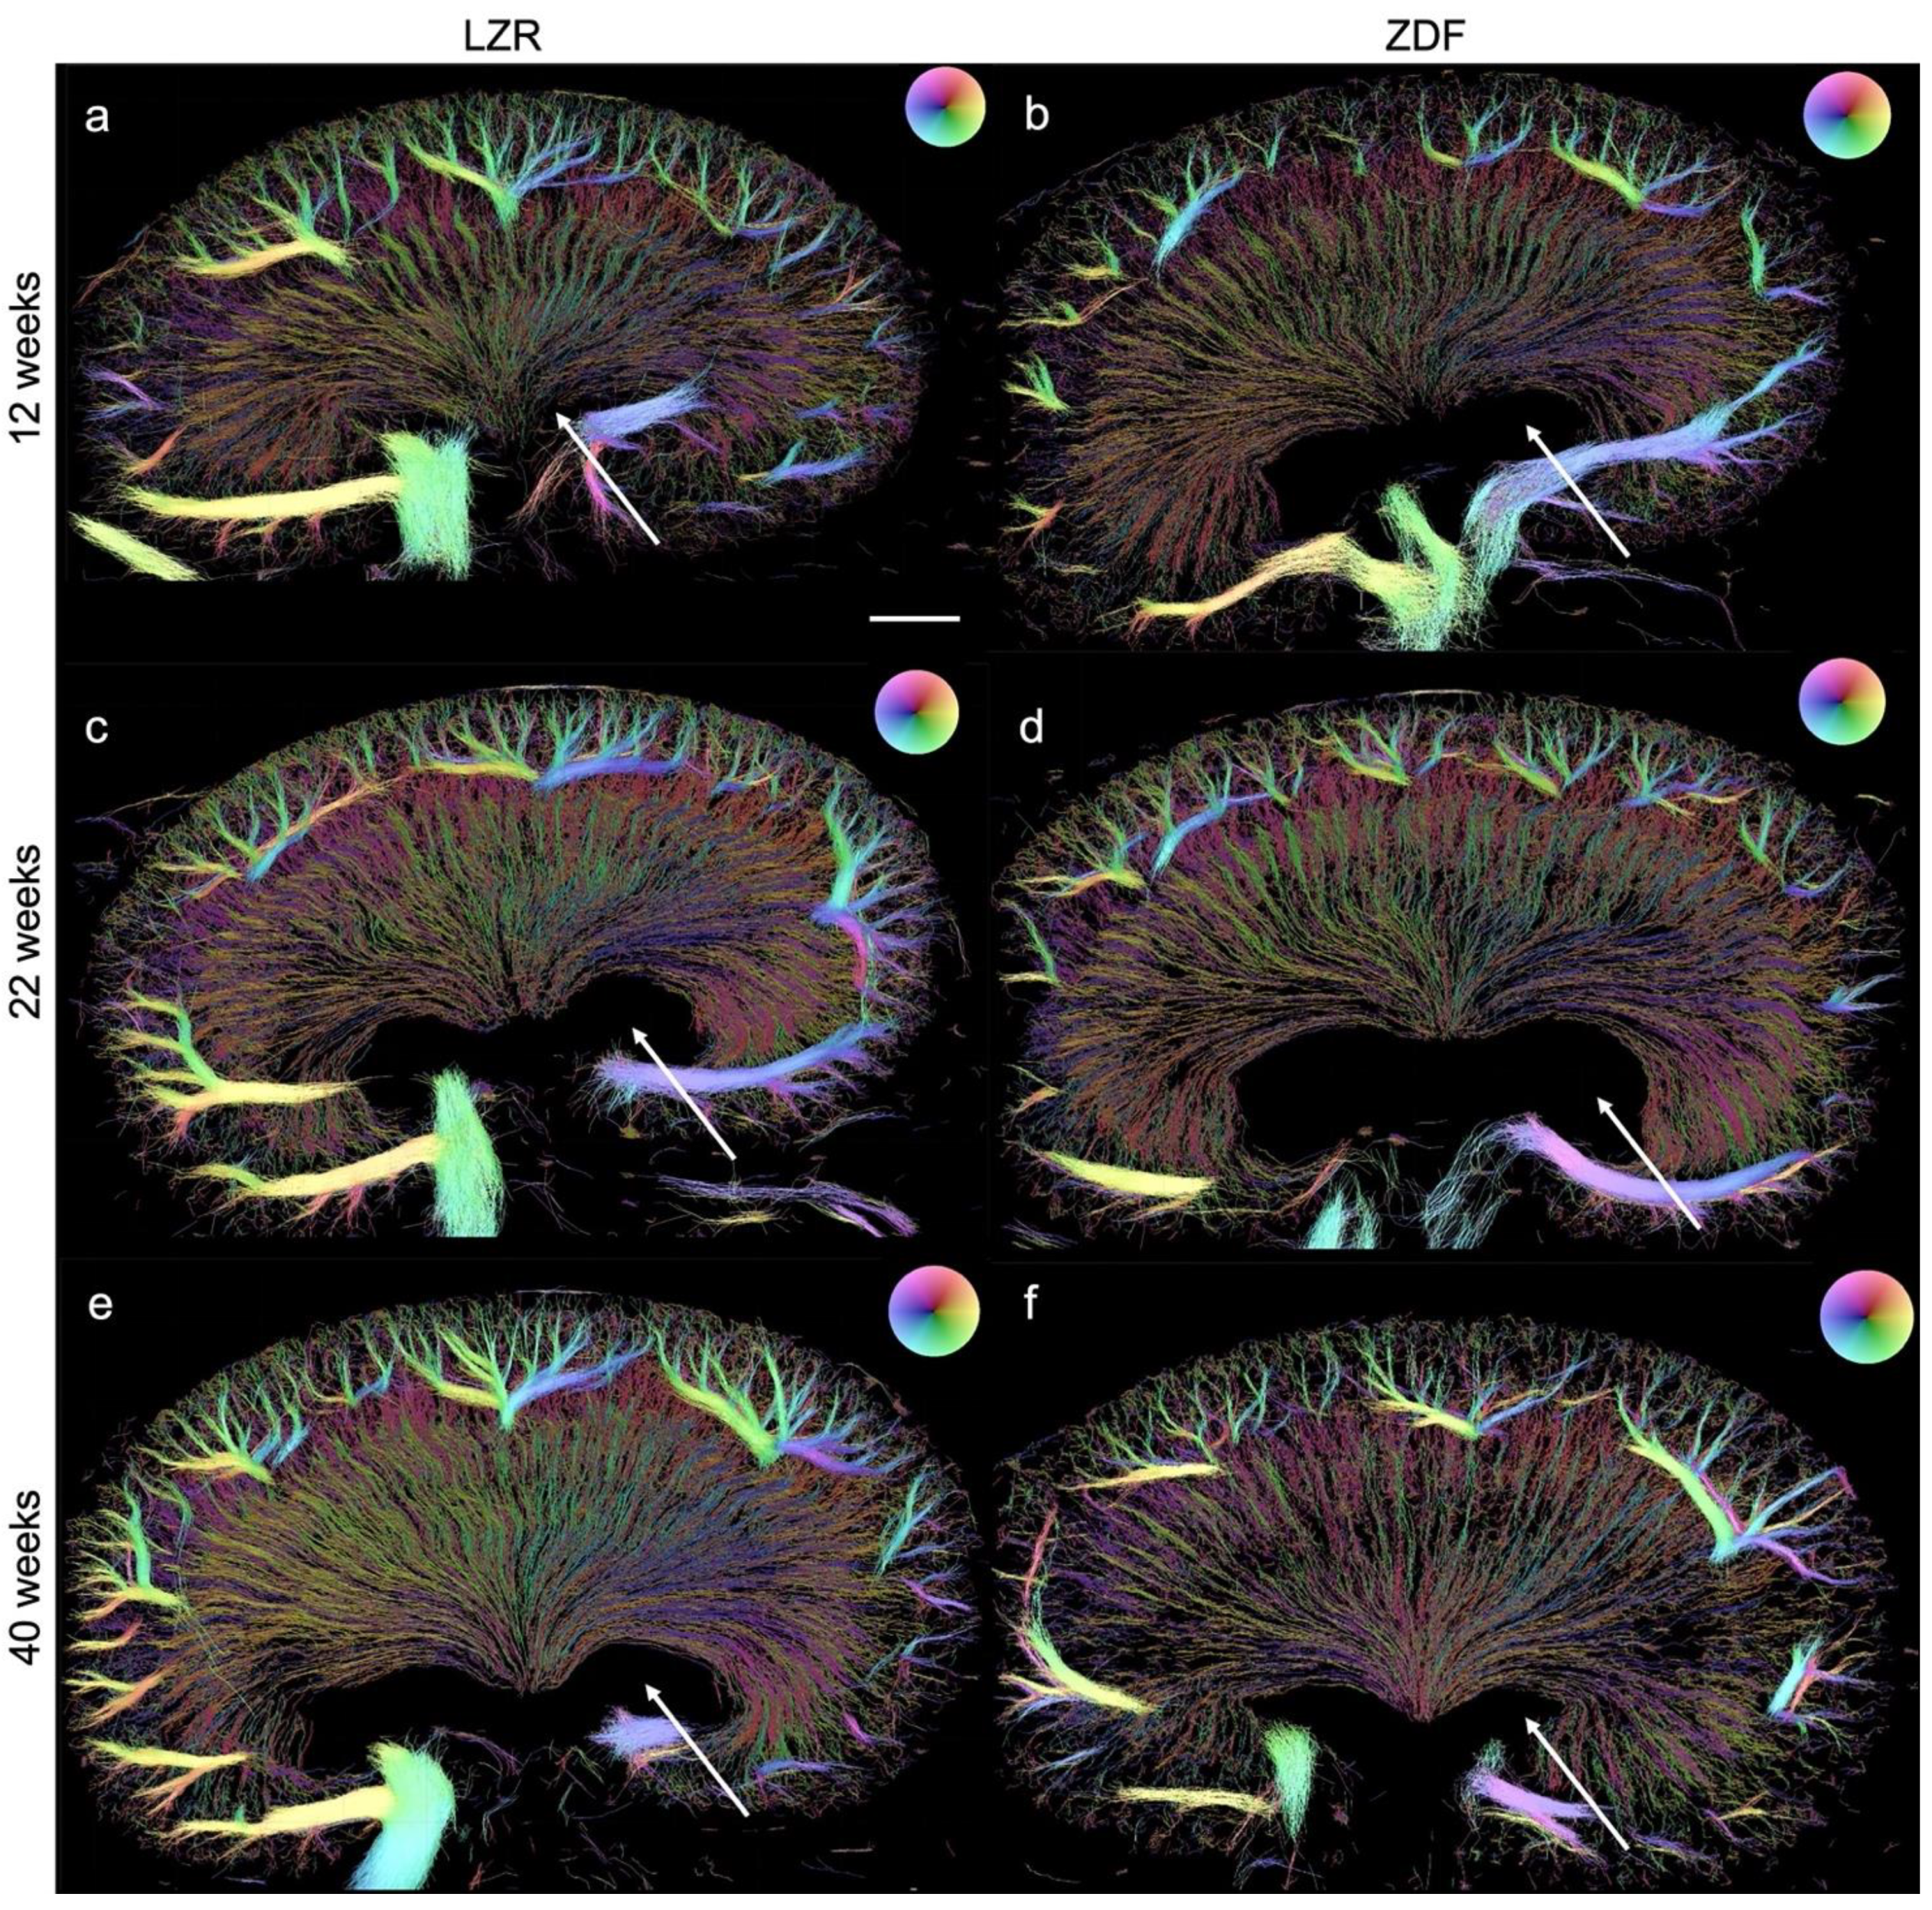

Figure 7.

SRUS images of kidneys from the Zucker diabetic fatty (ZDF) rats and the lean Zucker rats (LZRs) by weeks 12, 22, and 40. (b,d,f) illustrate a less dense renal vasculature in the ZDF rats compared with their age-matched LZR (a,c,e). Hydronephrosis (arrows) was found in all the kidneys examined. The direction of the MBs, hence the blood flow’s direction, is illustrated by the color wheel in the upper right corner, e.g., green color represents tracked MBs moving downwards, in the renal vein it correlates with blood flow out of the kidney. Scale bar in (a): 2 mm.

3.3. Quantified Measurements from SRUS

Examples of the SRUS images from each group are presented in Figure 7, showing the presence of hydronephrosis to various extents in all of the kidneys examined. The estimated mean vascular density is illustrated in Figure 8. The ZDF rats had a significantly decreased density in the CO at 22 weeks of age compared to the lean rats’ (p = 0.02). The same non-significant trend was seen at week 12 (p = 0.19). The high variance in density in the 40-week-old ZDF rats likely influenced the lack of a significant difference (p = 0.07). A significant decline in vascular density in the IM and OM of the ZDF rats was present by week 40 (p < 0.0001).